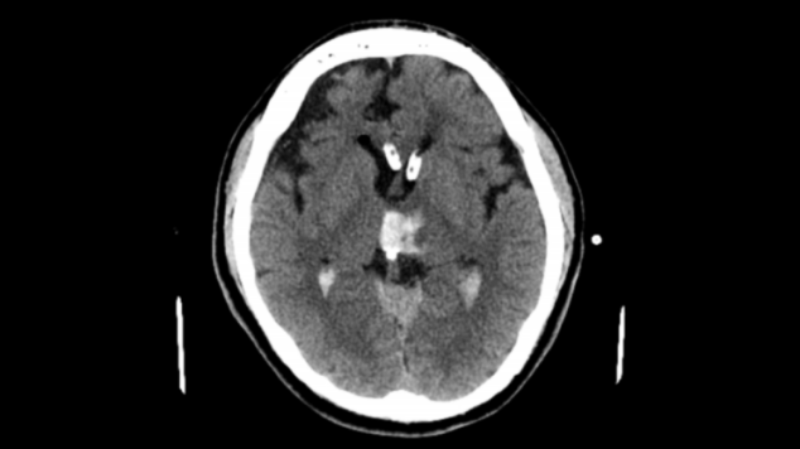

軟通道管道置入后

尿激酶溶解血腫第四天

拔除軟通道后-1

△軟通道后-2

醫(yī)生團隊在患者頭上畫好線,找準位置錐顱,置管進入,有淡紅色的血水從管子里流出來。固定好引流管后,連接上引流裝置。隨后根據(jù)腦里血腫的情況,每天往里面打一到兩次尿激酶,每次用的量在 5000 單位到 20000 單位不等。一直到血腫基本清除了,才把引流管拔掉。

術(shù)后患者恢復意識了,能正?;卮饐栴},也能按照指令做動作就轉(zhuǎn)到普通病房去了。